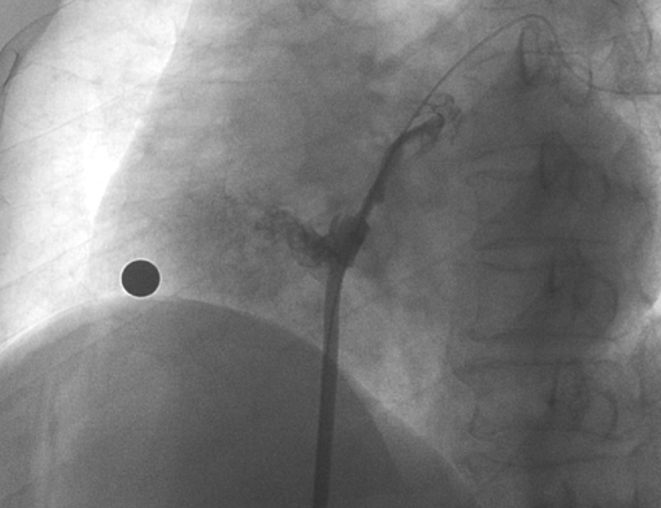

術中造影顯示患者為PFO且長隧道型,目前市場上已商業(yè)化的PFO封堵器難以滿足該患者解剖結構封堵需求。迪創(chuàng)醫(yī)療自主研發(fā)的OmniSeal PFO封堵器自適應性雙盤貼合設計能廣泛適應不同PFO隧道長度的解剖結構和形態(tài),其雙盤外包覆式阻流和隧道內填充阻流相結合的雙重阻流設計,可為此患者實現(xiàn)有效封堵。與此同時,OmniSeal首創(chuàng)的完全可穿刺式設計,也為此患者最大程度地保留了房間隔區(qū)域穿刺通道,以實現(xiàn)全兼容未來可能的左心系統(tǒng)二次介入術。術終造影和心臟超聲顯示封堵完全、效果良好。作為OmniSeal的首例臨床應用,本次手術的順利完成和優(yōu)異效果充分體現(xiàn)了產品的設計創(chuàng)新優(yōu)勢。

造影顯示長隧道型PFO